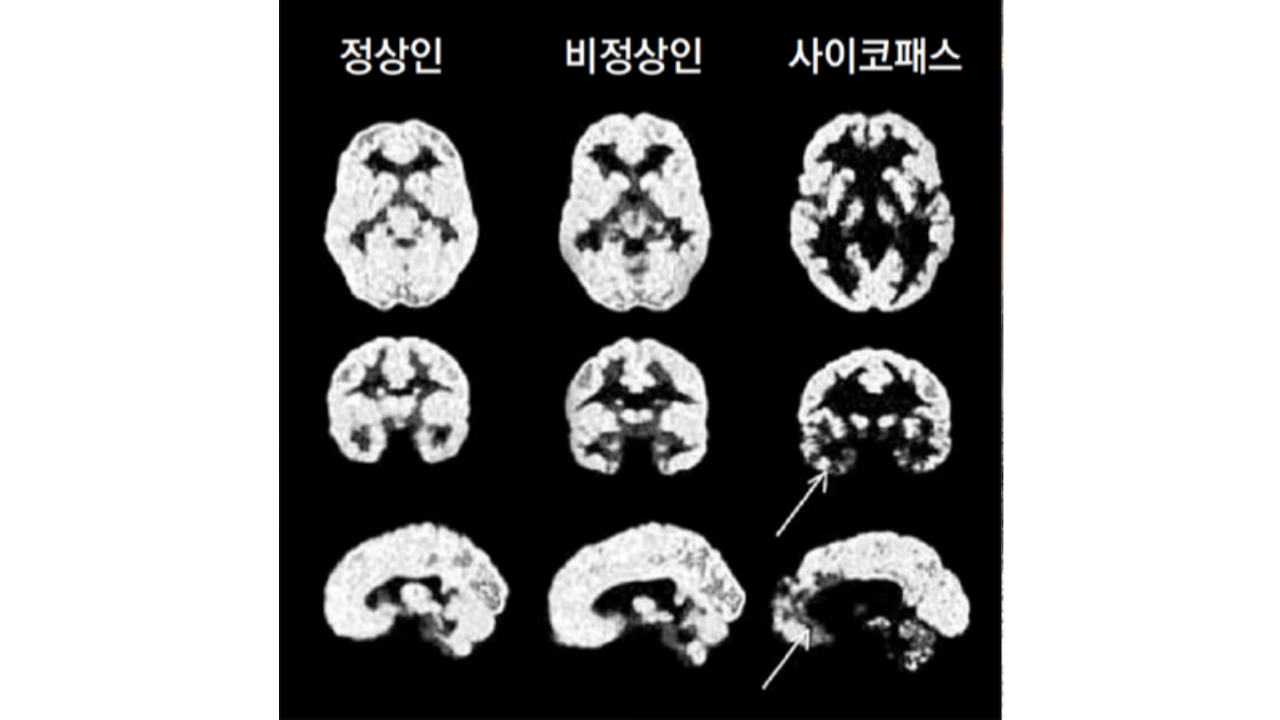

싸이코패스의 특징

싸이코패스는 감정 결여가 두드러지는 특징을 보여요. 이들은 타인의 감정을 이해하거나 공감하는 능력이 현저히 떨어지며, 자신의 행동이 타인에게 미치는 영향을 거의 고려하지 않아요.

싸이코패스 성향을 가진 사람들이 사회적으로 큰 성공을 거둘 수 있는 이유 중 하나는 감정을 조작하고 통제하는 능력이 뛰어나기 때문이에요. 이들은 겉으로 보기에는 정상인들과 크게 다르지 않기 때문에, 현재 우리와 함께 일상을 살아가고 있을 가능성이 높아요.